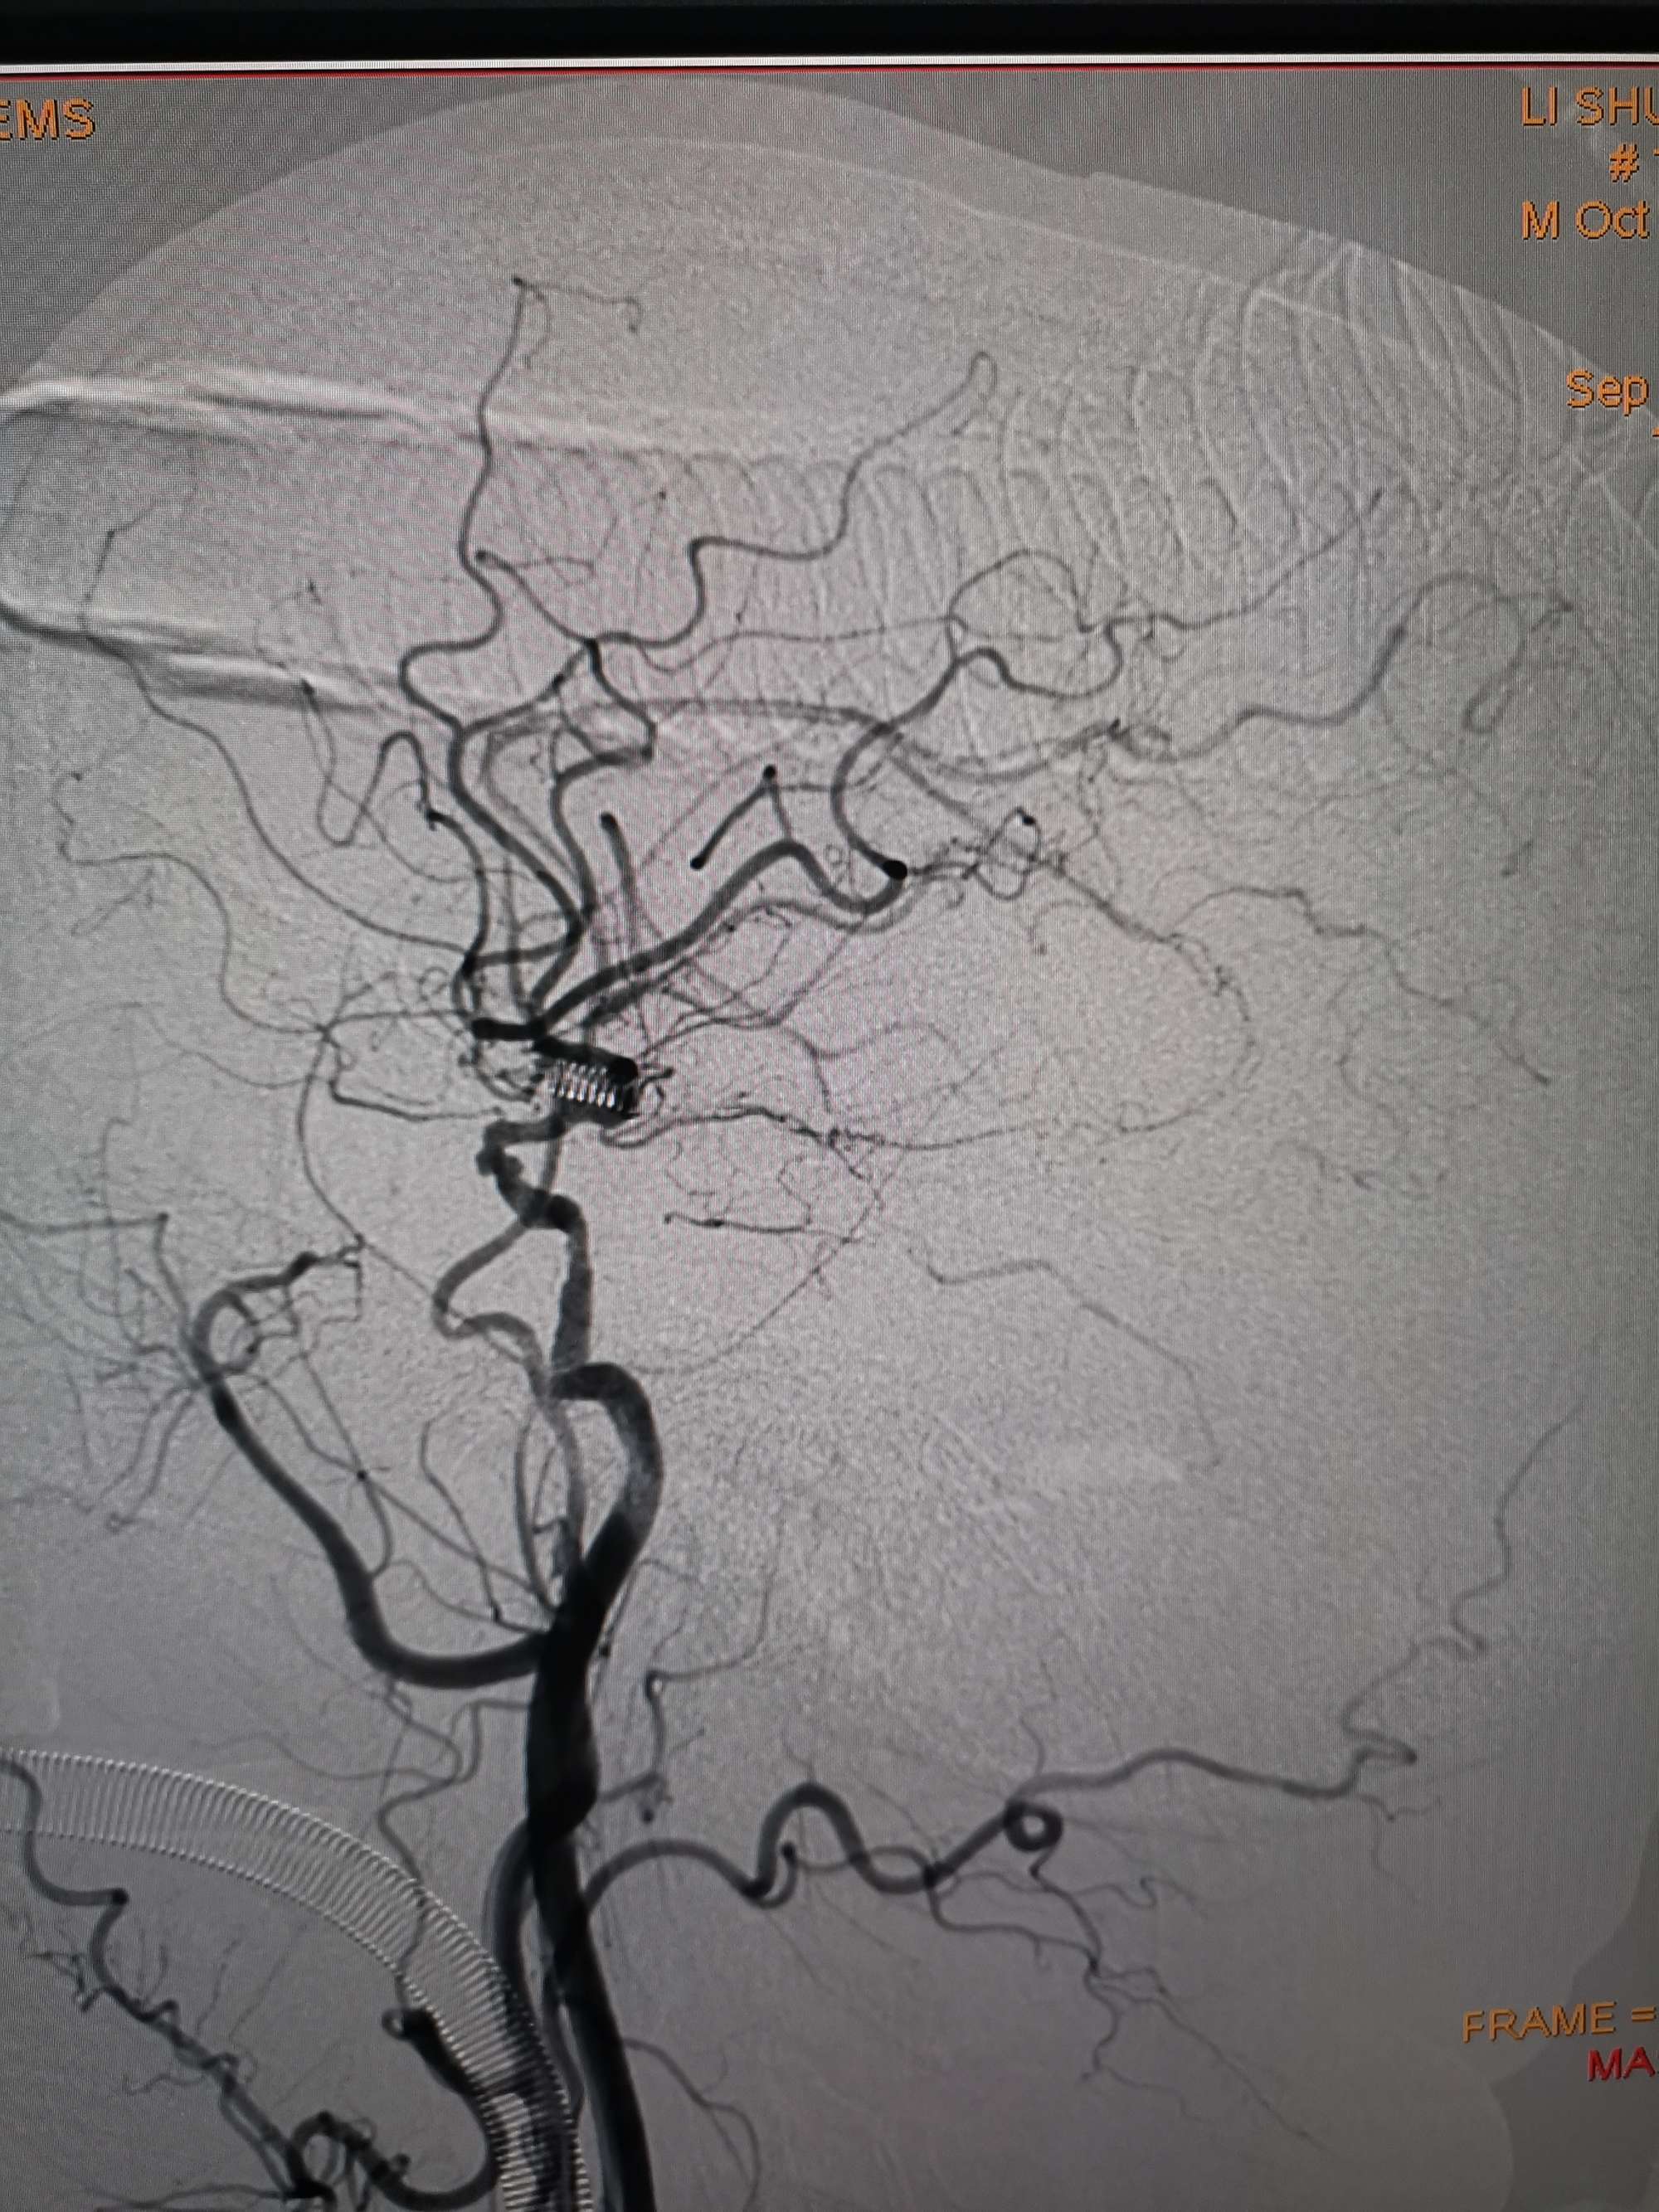

术后造影见左侧椎动脉闭塞段管腔恢复正常直径,远端血运良好。